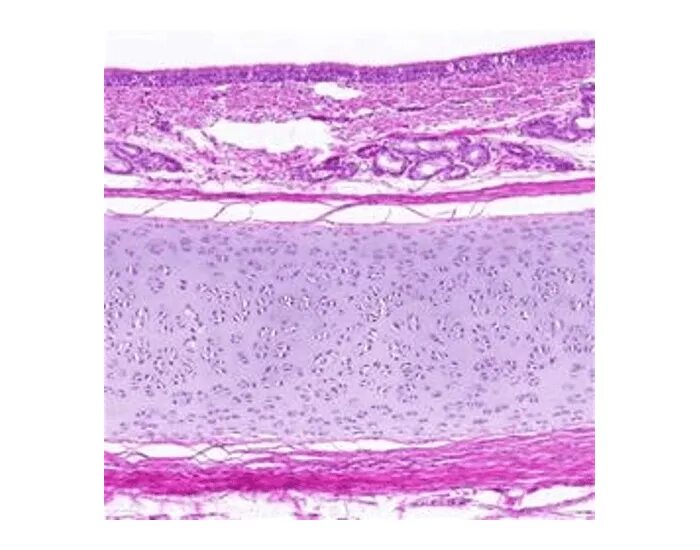

Трахея гистологический